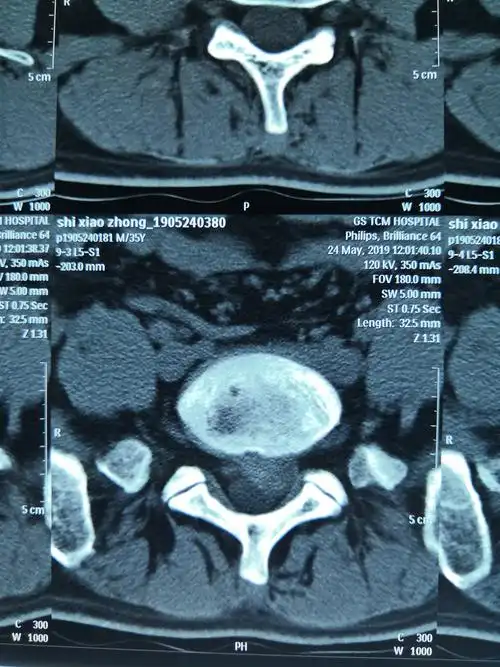

术前腰椎ct

腰椎间盘ct平扫(l5-s1)

腰椎ct